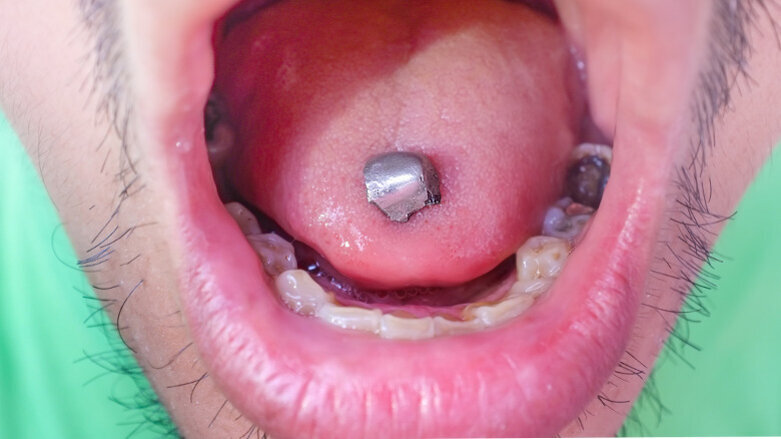

As pointed out by Multiple Sclerosis News Today, the agency has not banned the use of dental amalgam, or explicitly stated that it should not be used, but has updated its guidance and published a new information brochure on its use and removal in tooth restorations. The FDA does not recommend the removal or replacement of dental amalgam restorations that are in good condition.

The agency’s brochure states that “studies on people with dental amalgam do not show conclusive evidence that dental amalgam causes harmful health effects in the general population.”

Dental Tribune International reported in May that 9,287 pounds (4,212 kg) of mercury was used for dental amalgam in the U.S. in 2018. According to the U.S. Environmental Protection Agency, this accounted for 46.8% of the total elemental mercury that was used to make products in the country in that year.